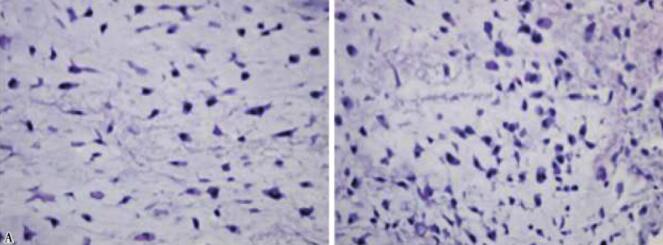

入院完善各项术前准备后行开颅肿瘤切除术,肿瘤达部分切除。术后患者恢复较好,无明显神经功能缺失。术后第一天CT(图2)示肿瘤部分切除。术后病理可见骨小梁(图3),病理报告为高分化软骨肉瘤。

图3术后病理可见骨小梁成分

A. 低倍镜;B. 高倍镜

颅底软骨肉瘤是一种少见的、生长缓慢、但有潜在致死性的肿瘤。年发病率为0.03/10万,约占所有颅底肿瘤的6%。多位于鞍旁结合部,起源于胚胎残余的软骨细胞,生长缓慢,好发于青壮年,女性多于男性。病理上分为3级(1级高分化,2级中等,3级低分化)。手术所见:肿瘤多位于硬膜外,呈灰白色或淡红色的半透明蘑菇状,质地较硬韧,也可伴有质软的胶冻黏液。局部骨质可受侵蚀破坏。高分化软骨肉瘤为偏良性肿瘤,对周围骨质往往是以推压性生长为主。镜下见:肿瘤组织主要由分化好的软骨细胞伴骨化、纤维组织、黏液成分构成。恶性软骨肉瘤软骨细胞大小不一,核大红染,毛细血管内皮细胞增生等改变。